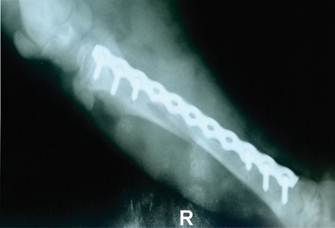

Antes de la intervención quirúrgica, se realizó los estudios complementarios, una radiografía convencional con vista lateral medial derecha de la extremidad fracturada (Figura 1). Previamente se realizó los exámenes pre quirúrgicos como, hemograma completo, perfil renal, perfil hepático para evaluar el riesgo, estando estos en los parámetros normales (Tabla 1 y 2).

En la imagen radiográfica se observó una fractura cerrada completa oblicua corta o bisel cortó en tibia y peroné en la diáfisis proximal (Figura 1), fractura de baja energía descripción y codificación que corresponde según el sistema de clasificación AO VET morfológico y alfanumérico de la clasificación de fracturas (AO Cirugía Veterinaria de referencia) es de clasificación de tipo 41-A211.

Figura 5 alineaciones en el plano sagital en la proyección mediolateral, placa bloqueada de holes de 9 mm y tornillos de bloqueo de 3.2 mmx12 mm, 8 mm